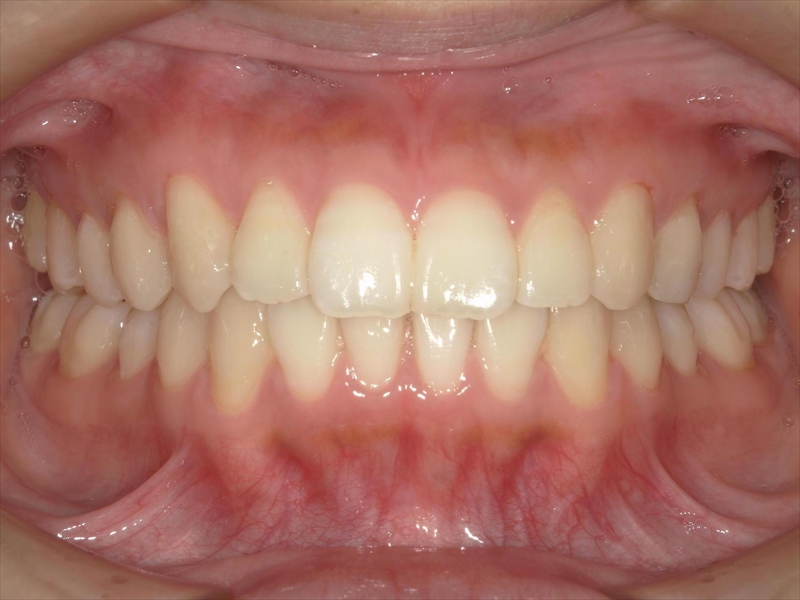

この患者様は、重度の出っ歯があり、下顎前歯には叢生が認められました。

また、奥歯の噛み合わせにも問題があり、本来は半歯分ずつずれて噛み合うべきところが、正しく機能していない状態でした。

前歯を収めるスペースを確保するために歯を削り(IPR)、奥歯から順に後方(奥)へ下げる並びを整える計画を立案いたしました。

治療前後 写真